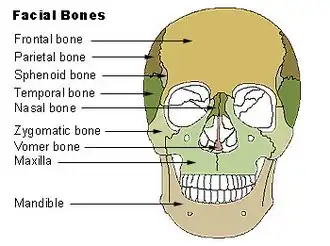

Facial bones.

Facial bones. -